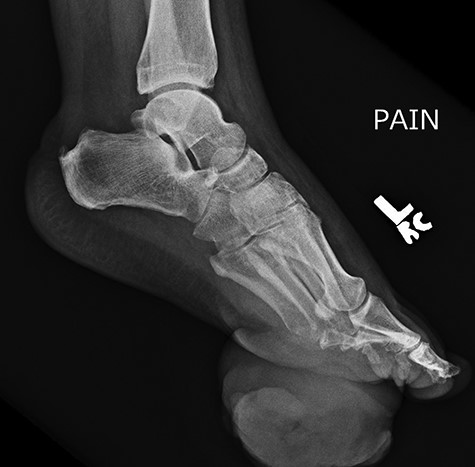

On physical examination, the only significant findings included morbid obesity and a ‘small red tender lesion’ resembling an ‘abscess or fluid collection at the bottom of his foot’ (Fig. 1). X-ray of the patient’s foot was interpreted as ‘soft tissue swelling’ (Fig. 2). The patient was treated with antibiotics for the initial impression of cellulitis and sepsis.

Initial x-ray of the foot was interpreted as ‘soft tissue swelling of the foot’.

Repeat lateral X-ray views of the foot, 2 months later, showed ‘interval appearance of large soft tissue mass, plantar to the phalanges’. The differential diagnostic consideration by the imaging studies included ‘phlegmon, abscess, hematoma, or less likely a rapidly growing neoplasm’.

Approximately 2 months following surgical excision of the tumor, the patient presented with a significantly enlarged and painful recurrence of the mass (Fig. 5). Repeat X-rays of the foot showed ‘interval large soft tissue mass’ (Fig. 6). Nuclear three-phase bone scan was ‘suspicious for osteomyelitis or tumor involvement of bone’.